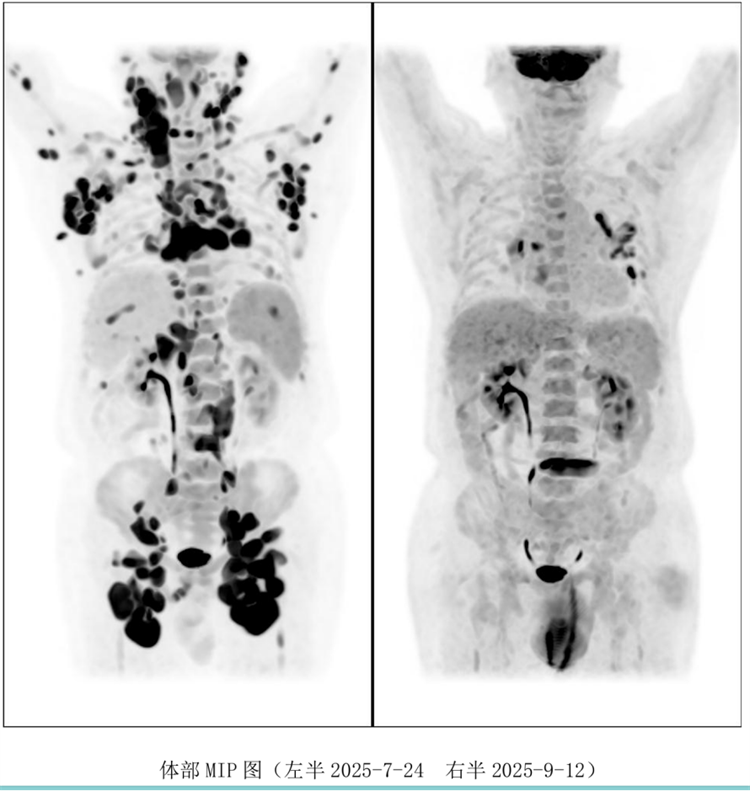

病例匯報(bào)環(huán)節(jié)由我院淋巴瘤科張薇醫(yī)生帶來了三例精彩紛呈的難治復(fù)發(fā)彌漫大B淋巴瘤CAR-T治療的病例。

病例過程跌宕起伏,從橋接治療到靶點(diǎn)的選擇,并發(fā)癥的處理都極具代表性。張醫(yī)生詳盡分享了患者在治療過程中的挑戰(zhàn)、決策依據(jù)以及CAR-T細(xì)胞治療后的驚人緩解與轉(zhuǎn)歸,充分展示了CAR-T技術(shù)為晚期患者帶來的突破性生存希望。